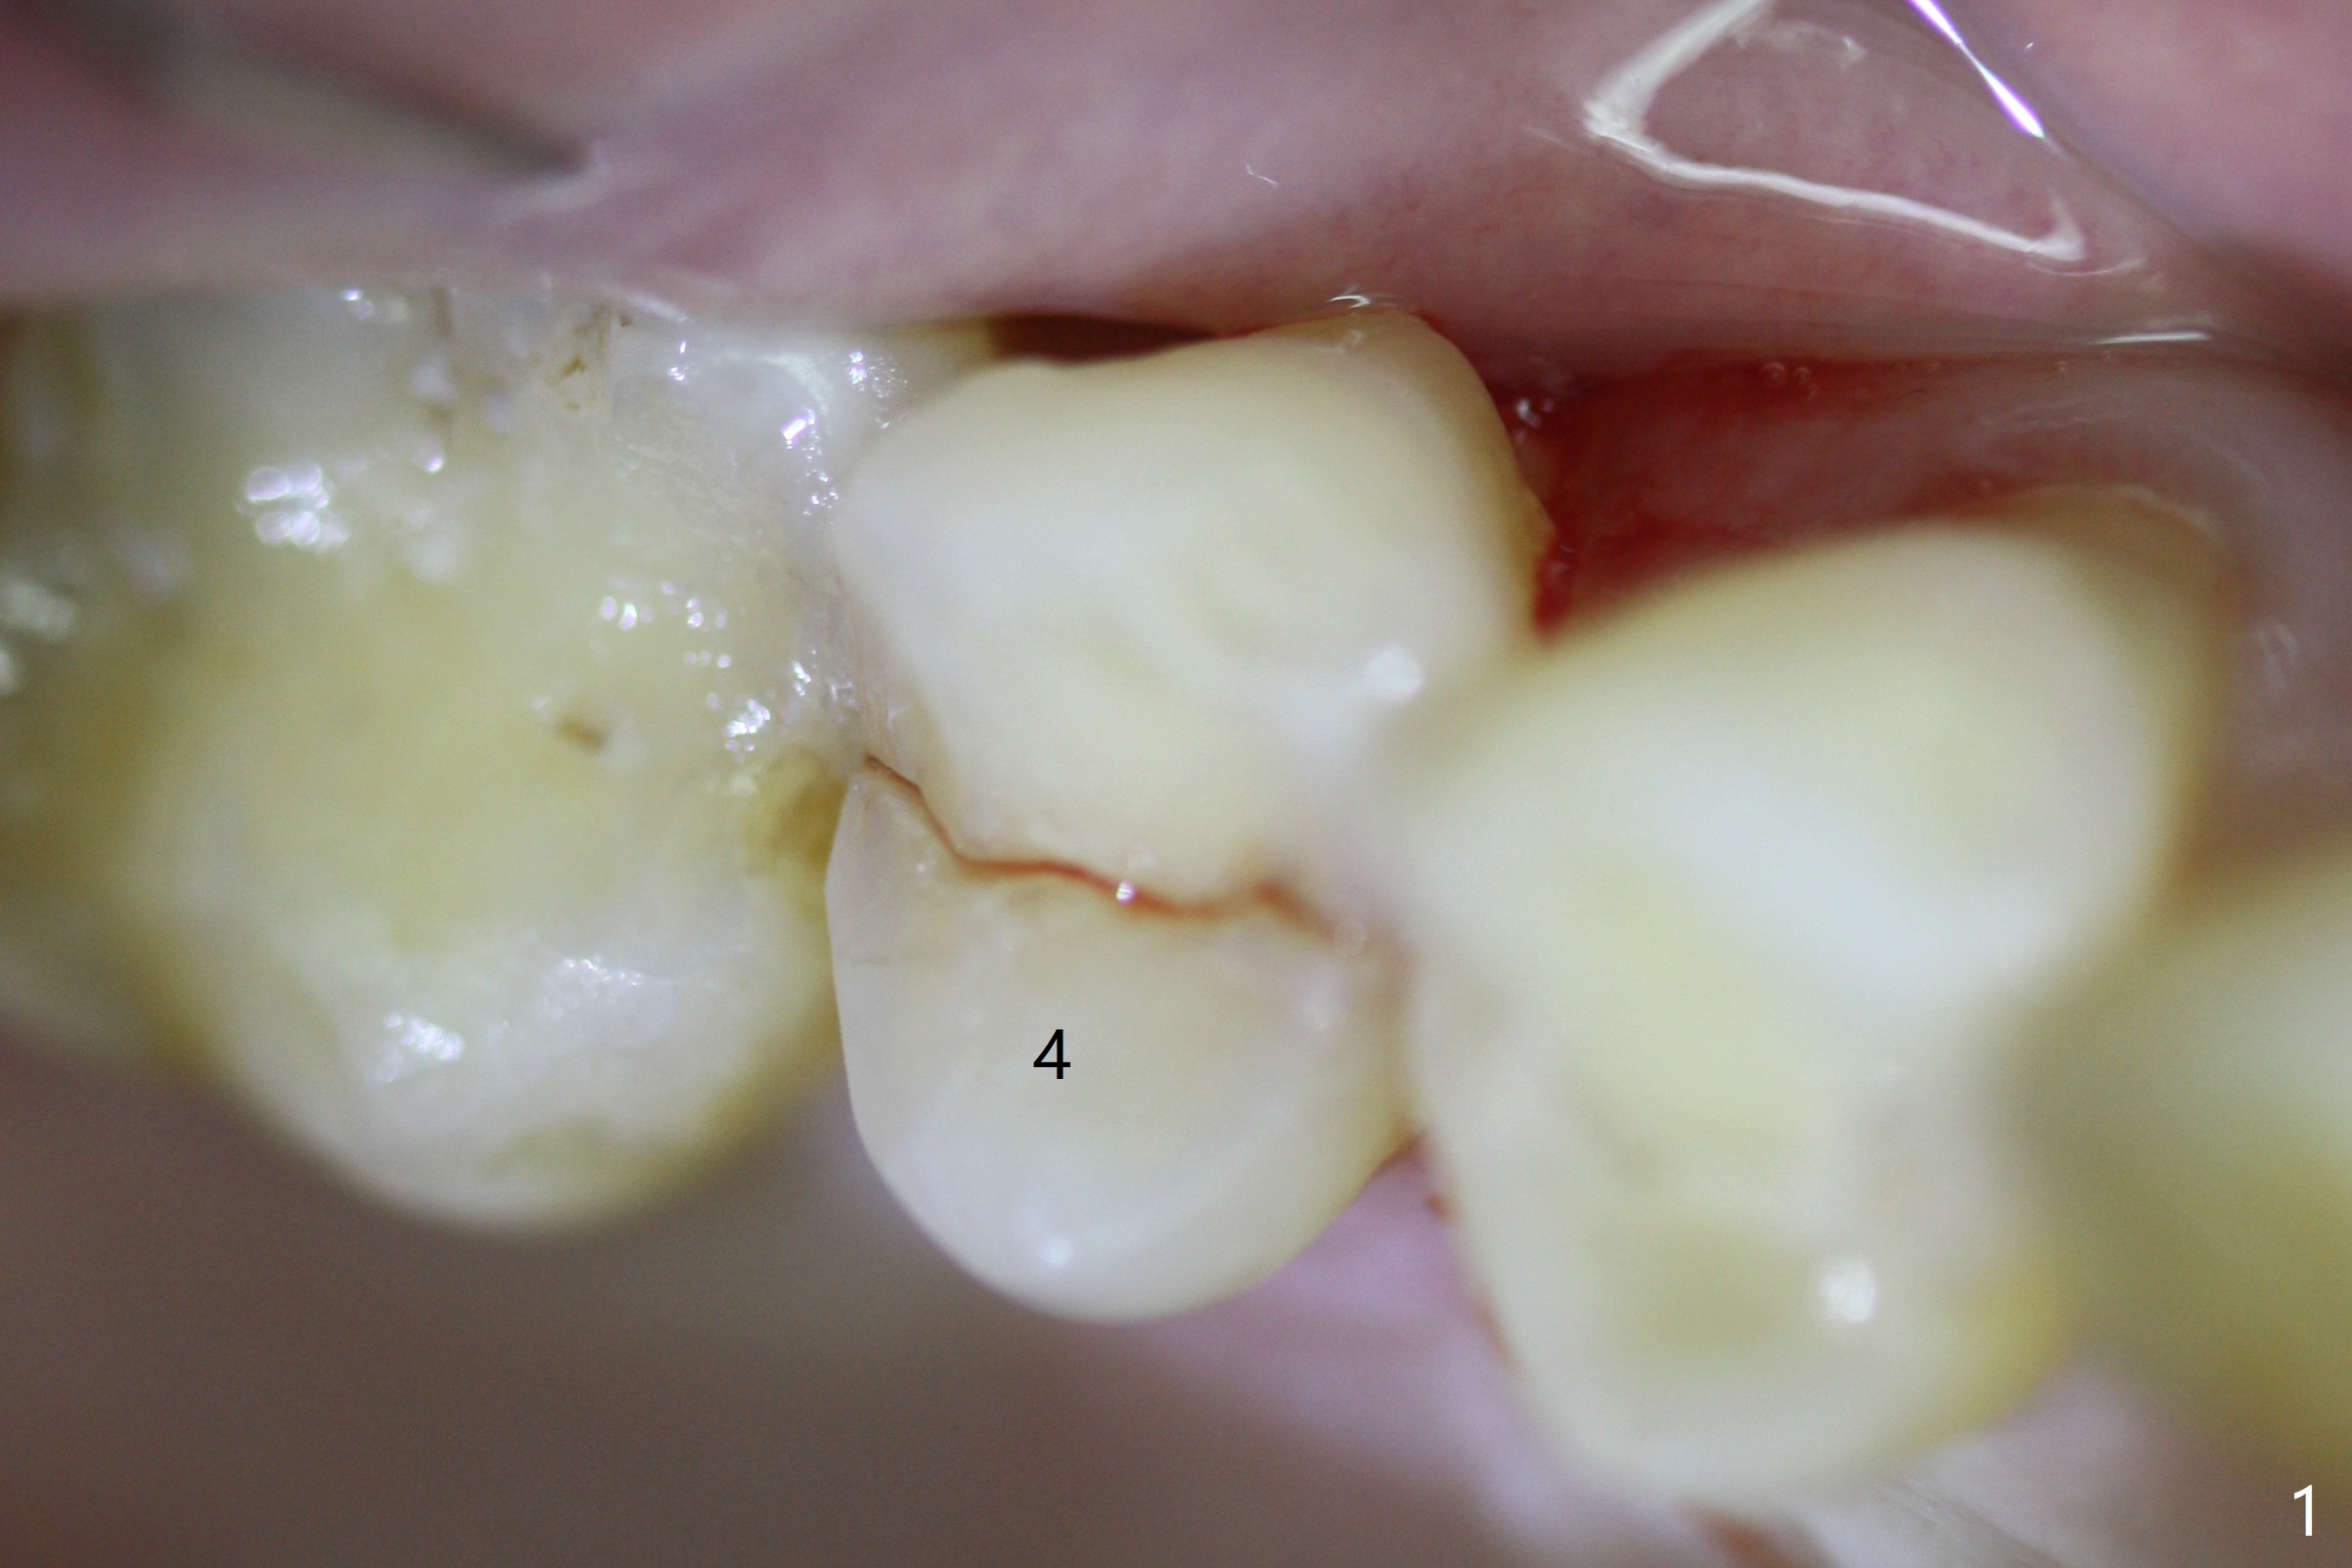

A 61-year-old man cracks the tooth #4 while chewing on a piece of chicken bone (Fig.1,2). Initial osteotomy appears to be able to hold a 16 mm long implant (Fig.3). After sequential osteotomy, a 4x16 mm implant is initially unable to be seated low enough for the buccal crest. Following packing the osteotomy with Vanilla Graft (.5-1 mm) and additional 2-3 mm depth of osteotomy, the implant is placed slightly apical to the buccal crest (Fig.4,5); with placement of Vanilla Graft (*) and a 4.5x4(4) mm abutment, an immediate provisional is fabricated to close the socket. The provisional is removed 3 months postop because of poor local oral hygiene (Fig.6,7). The gingiva is healthy 2-3 weeks later; it is easy to take impression (Fig.8).